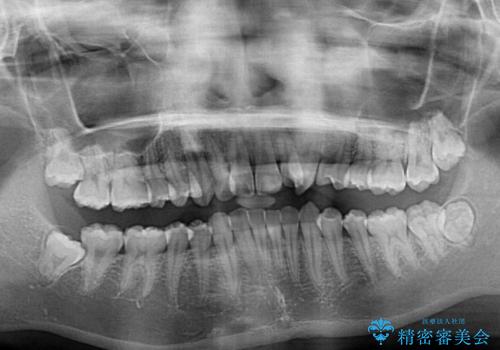

- 咬み合わせが悪いとのことで来院された患者様です。

ぱっと見はインビザラインによる矯正治療も可能と思われましたが、歯根が最も長い犬歯がクロスバイトになっており、インビザラインでは対応困難と判断され、ワイヤー装置にて矯正治療を行うこととしました。

クロスバイトになっている犬歯は、歯の移動に伴い装置を張り替えていくことで対応することとしました。

クロスバイト改善中には歯髄壊死を起こすリスクがあるため、神経に問題がないか確認しながら治療を進めて行く必要があります。

思っていたよりも早くクロスバイトは改善され、歯髄壊死に至ることなく、無事に治療を終えることができました。